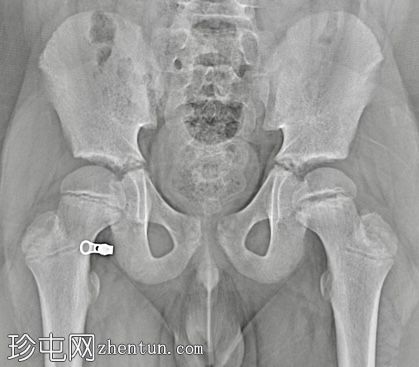

X线片

左侧股骨骨骺增宽且不规则。

急诊X线片显示可能存在股骨骨骺骨折,因此需要入院并进行皮肤牵引。入院后,CT扫描证实为左侧股骨股骨头骨骺滑脱。手术固定安排在次日进行。

诊断主要依靠影像学检查,通常采用髋关节正位和蛙式侧位片。治疗方法一般包括原位经皮克氏针固定,以防止进一步滑脱,从而降低股骨头坏死和软骨溶解的风险。